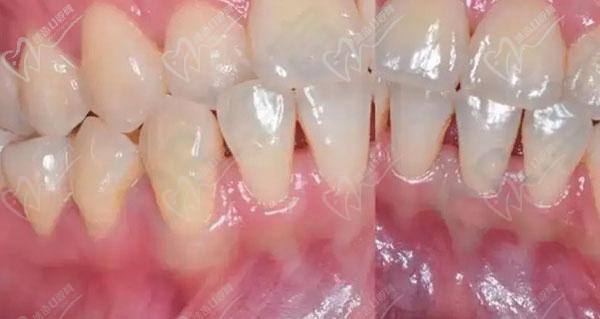

植骨时机需个体化设计:常见方案有三种,一是正畸前植骨(引导骨再生GBR),先植骨等待3-6个月骨结合完成后再正畸,适用于骨量严重不足者;二是正畸中植骨,在牙齿移动过程中同步进行局部植骨,缩短治疗周期;三是正畸后植骨,针对矫正后美学区骨量不足,改善牙龈形态,无论哪种方案,术后均需保持口腔卫生,避免咀嚼硬物,定期复查骨愈合情况。

牙槽骨薄患者的正畸治疗需多学科协作,正畸医生与口腔外科医生共同制定方案,既保证牙齿排齐美观,又确保骨组织健康,治疗期间患者需严格遵医嘱,定期复查,及时调整治疗方案,才能获得长期稳定的矫正效果。